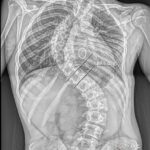

Lise öğrencisi Eren Sayın’ın, 4 yaşında kalp yetmezliği olduğu ortaya çıktı ve kalbindeki delik nedeniyle ilk ameliyatını oldu. 4 yaşında bu yana ilaç kullanan Eren, 1 yıl önce bu kez mitral kapak değişimi operasyonu geçirdi. Kalp rahatsızlığı ile birlikte skolyozu da bulunan Eren, ağrıları artından Ankara Etlik Şehir Hastanesi’ne başvurdu. Eren’in sırt bölgesinde 90, bel bölgesinde 70 dereceye ulaşan eğrilik tespit edildi. Eren, kalp kapağı ameliyatı nedeniyle kullandığı kan sulandırıcı ilaçlar kesilmeden biri 8 saat, diğeri 6 saat olmak üzere 2 seanslık riskli operasyonla skolyozdan kurtuldu. Eren, yüksek miktarda kan kaybı yaşamasına rağmen başarılı geçen operasyonun ardından sağlığına kavuştu.

Ameliyatı gerçekleştiren Etlik Şehir Hastanesi Ortopedi ve Travmatoloji Uzmanı Doç. Dr. Vedat Biçici, Eren’in kalp rahatsızlığı nedeniyle skolyozunun son dönemde hızlı ilerlediğinin tespit edildiğini söyleyerek, “Kalpteki problemlerinden dolayı riskli bir hastaydı. İlk ameliyatında ciddi kanaması olmasından dolayı ilk ameliyatını birinci seans olarak tamamlayamadan bitirmek zorunda kaldık. İmplantlarını yerleştirip, ameliyatı sonlandırdık. Genel durumu toparladıktan sonra birkaç hafta geçip, değerleri de normal değerlere geldikten sonra ikinci seans olarak tekrar ameliyata aldık. İkinci seansta omurgadaki düzeltme işlemlerini tamamlayıp operasyonumuzu bitirdik” diye konuştu.

Doç. Dr. Biçici, skolyoz cerrahisinin diğer cerrahilere göre daha riskli, daha zor olduğunu söyleyerek, “Çünkü omuriliğe çok yakın çalışmanız gerekiyor ve yerleştirdiğiniz implantlar yüzünden bazen milimetre düzeyinde yakın çalışıyorsunuz. Omurgayı düzeltirken omuriliğe hasar verme ya da omuriliğe bir problem oluşma ihtimali yüksek. Ondan dolayı riskli bir ameliyattır. Zaten cerrahi süresi uzun ve geniş bir alanda ameliyat yaptığınızdan dolayı bunlar hep riski artıran şeylerdir. Eren ayrıca kan sulandırıcı ilaç alıyor. Bunlar kesilemediğinden bu ilaçların etkisi altında ameliyata almak zorunda kaldık. Normalde bu ilaçlar ameliyat öncesinde kesilir, kanama riski azaltılır. Ama Eren’de bunu yapamadık. Bu da Eren’in ilk ameliyatta kan kaybını artırdı. İlk ameliyatta ciddi kan kaybı yaşadık, operasyonu yarıda bırakmak zorunda kaldık. Kan tablosu normal değerlere geldikten sonra ikinci seans ameliyata aldık. Onun için daha güvenli olacak şekilde iki aşamada ameliyatını tamamladık. Şu an durumu iyi. Fizik tedaviye başlayacak ve kademeli olarak normal hayatına dönecek” dedi.